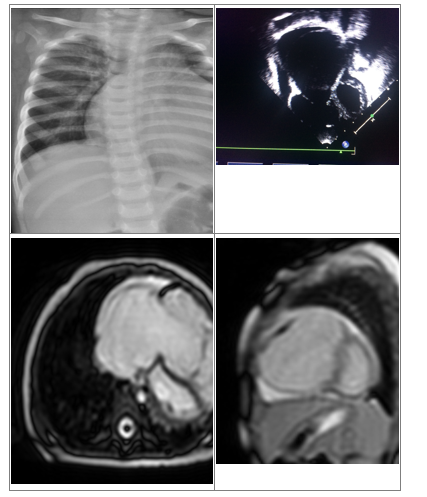

A suspicion of Uhl’s anomaly was made, so a CMR (cardiac magnetic resonance) imaging was done which confirmed Echo findings of dilated RA, RV (RVEDV-123ml/m2) with severe tricuspid regurgitation. Poor right ventricular function (RV EF-15%) with thin free wall with flattened inter-ventricular septum during diastole. There was no evidence of fibro-fatty RV wall infiltration, thus ruling out ARVD. On delayed enhancement imaging, there was enhancement along the RV free wall, apical RV and RV portion of the distal IVS (Figure 1). Min- imal pericardial effusion was present. The CMR (cardiac magnetic resonance) findings con- firmed Uhl’s anomaly and parents were counselled about the management options and they did not prefer surgical palliation. The child was discharged on diuretics and ACE inhibitors and is in follow up without any symptoms presently.

Figure 1 A: CXR showing cardiomegaly;

B: 2D Echo showing dilated RA and RV;

C and D: CMR images showing dilated RA, RV with thin RV free wall.

Case 2: 2 years old apparently asymptomatic boy was referred to us with an incidental murmur. On examination his vitals were normal with HR: 98/mins regular, RR-20/min, BP: 102/64 mm Hg, saturation in room air: 94%. Apex was in the 5th intercostal space 1 cm lateral to the midclavicular line. The first heart sound was normal in intensity and duration and the second heart sound was normal in intensity with normal splitting. A soft systolic murmur was present at the left lower sternal border. CXR showed mild cardiomegaly. Echocardiography showed dilated RA and RV with severe tricuspid regurgitation and right ventricular dysfunction. A diagnosis of organic TR was made, diuretics were started and the child was under follow up. The child developed features of congestive heart failure. CMR (cardiac magnetic resonance) imaging was done which showed dilated RA, RV with thinned out RV wall with- out any fatty infiltration of the RV wall, suggesting Uhl’s anomaly (Figure 2). Parents were in- formed about the condition and prognosis and they too preferred medical management over the palliative surgical procedure.

Figure 2 A: 2 Echo with colour showing dilated RA and RV with colour doppler showing severe TR;

B: CMR images showing dilated RA, RV with thin RV free wall.